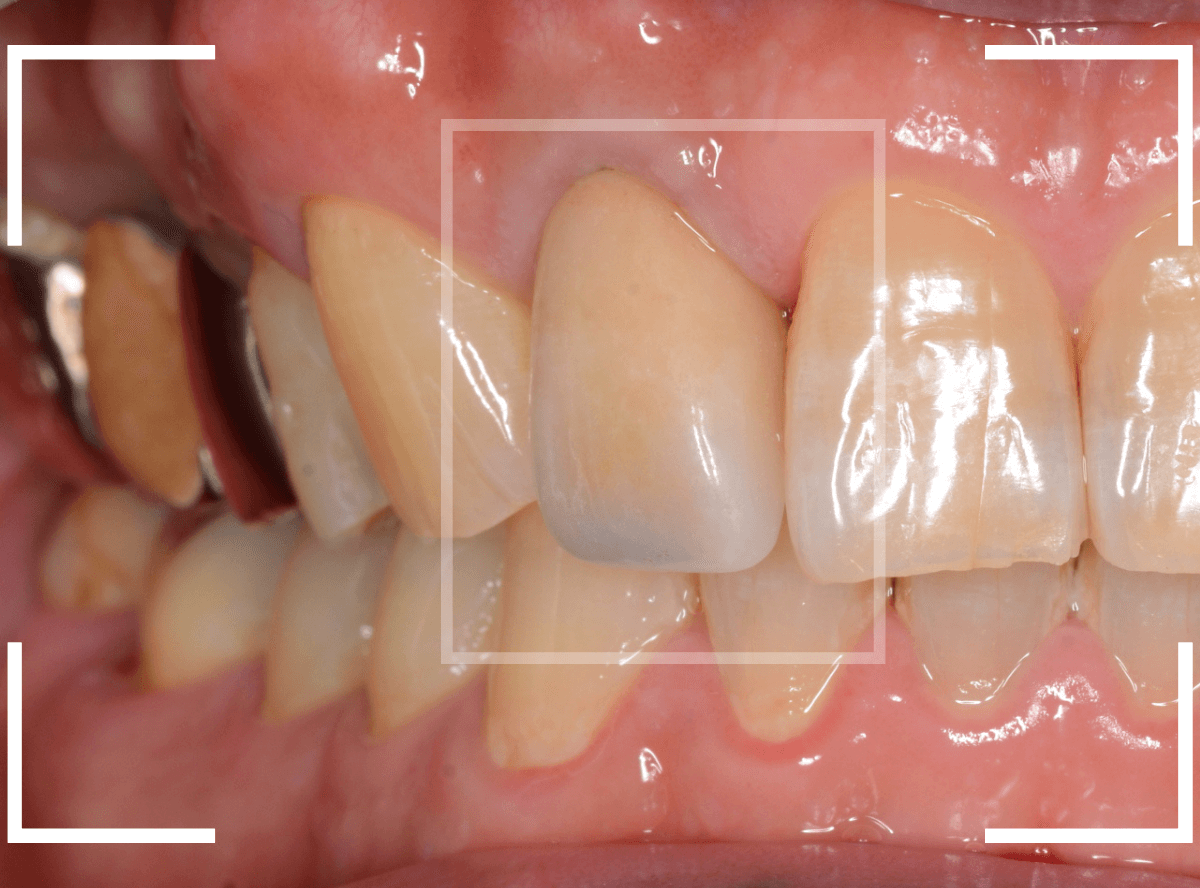

Case.16 保険のさし歯(レジン前装冠)をジルコニア・セラミックへ

以前に治療した上のさし歯を綺麗にやり直したいというご相談の患者さんです。

保険診療で行うさし歯「レジン前装冠」が入っています。

「レジン前装冠」は裏から撮影した写真を見ていただければわかるように、銀歯の上にレジン(プラスチック)を盛ったさし歯で、実質的には銀歯です。

銀歯の上にプラスチックを盛るために、歯をかなり大きく削る必要があったり、短期間で劣化・変色する(この方の差し歯も劣化してのっぺりした黄土色になっています)、金属の色素が歯肉に溶け出して歯肉が黒くなる(メタル・タトゥー)などのデメリットがあります。